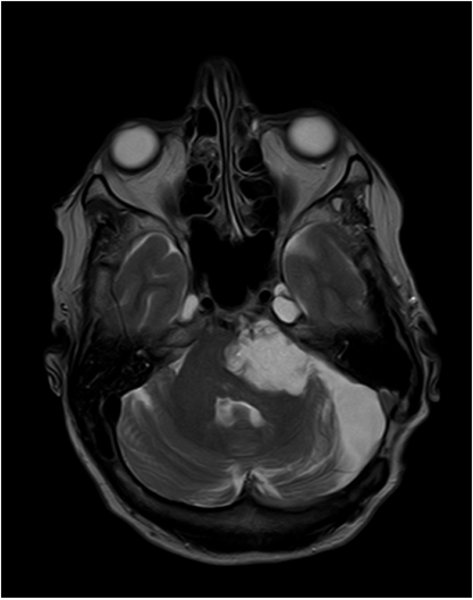

Epidermoid - T2 - axial

Liquorintenses Signal in T2

DD: Arachnoidalzyste, mit  Liquorsignal in allen Sequenzen